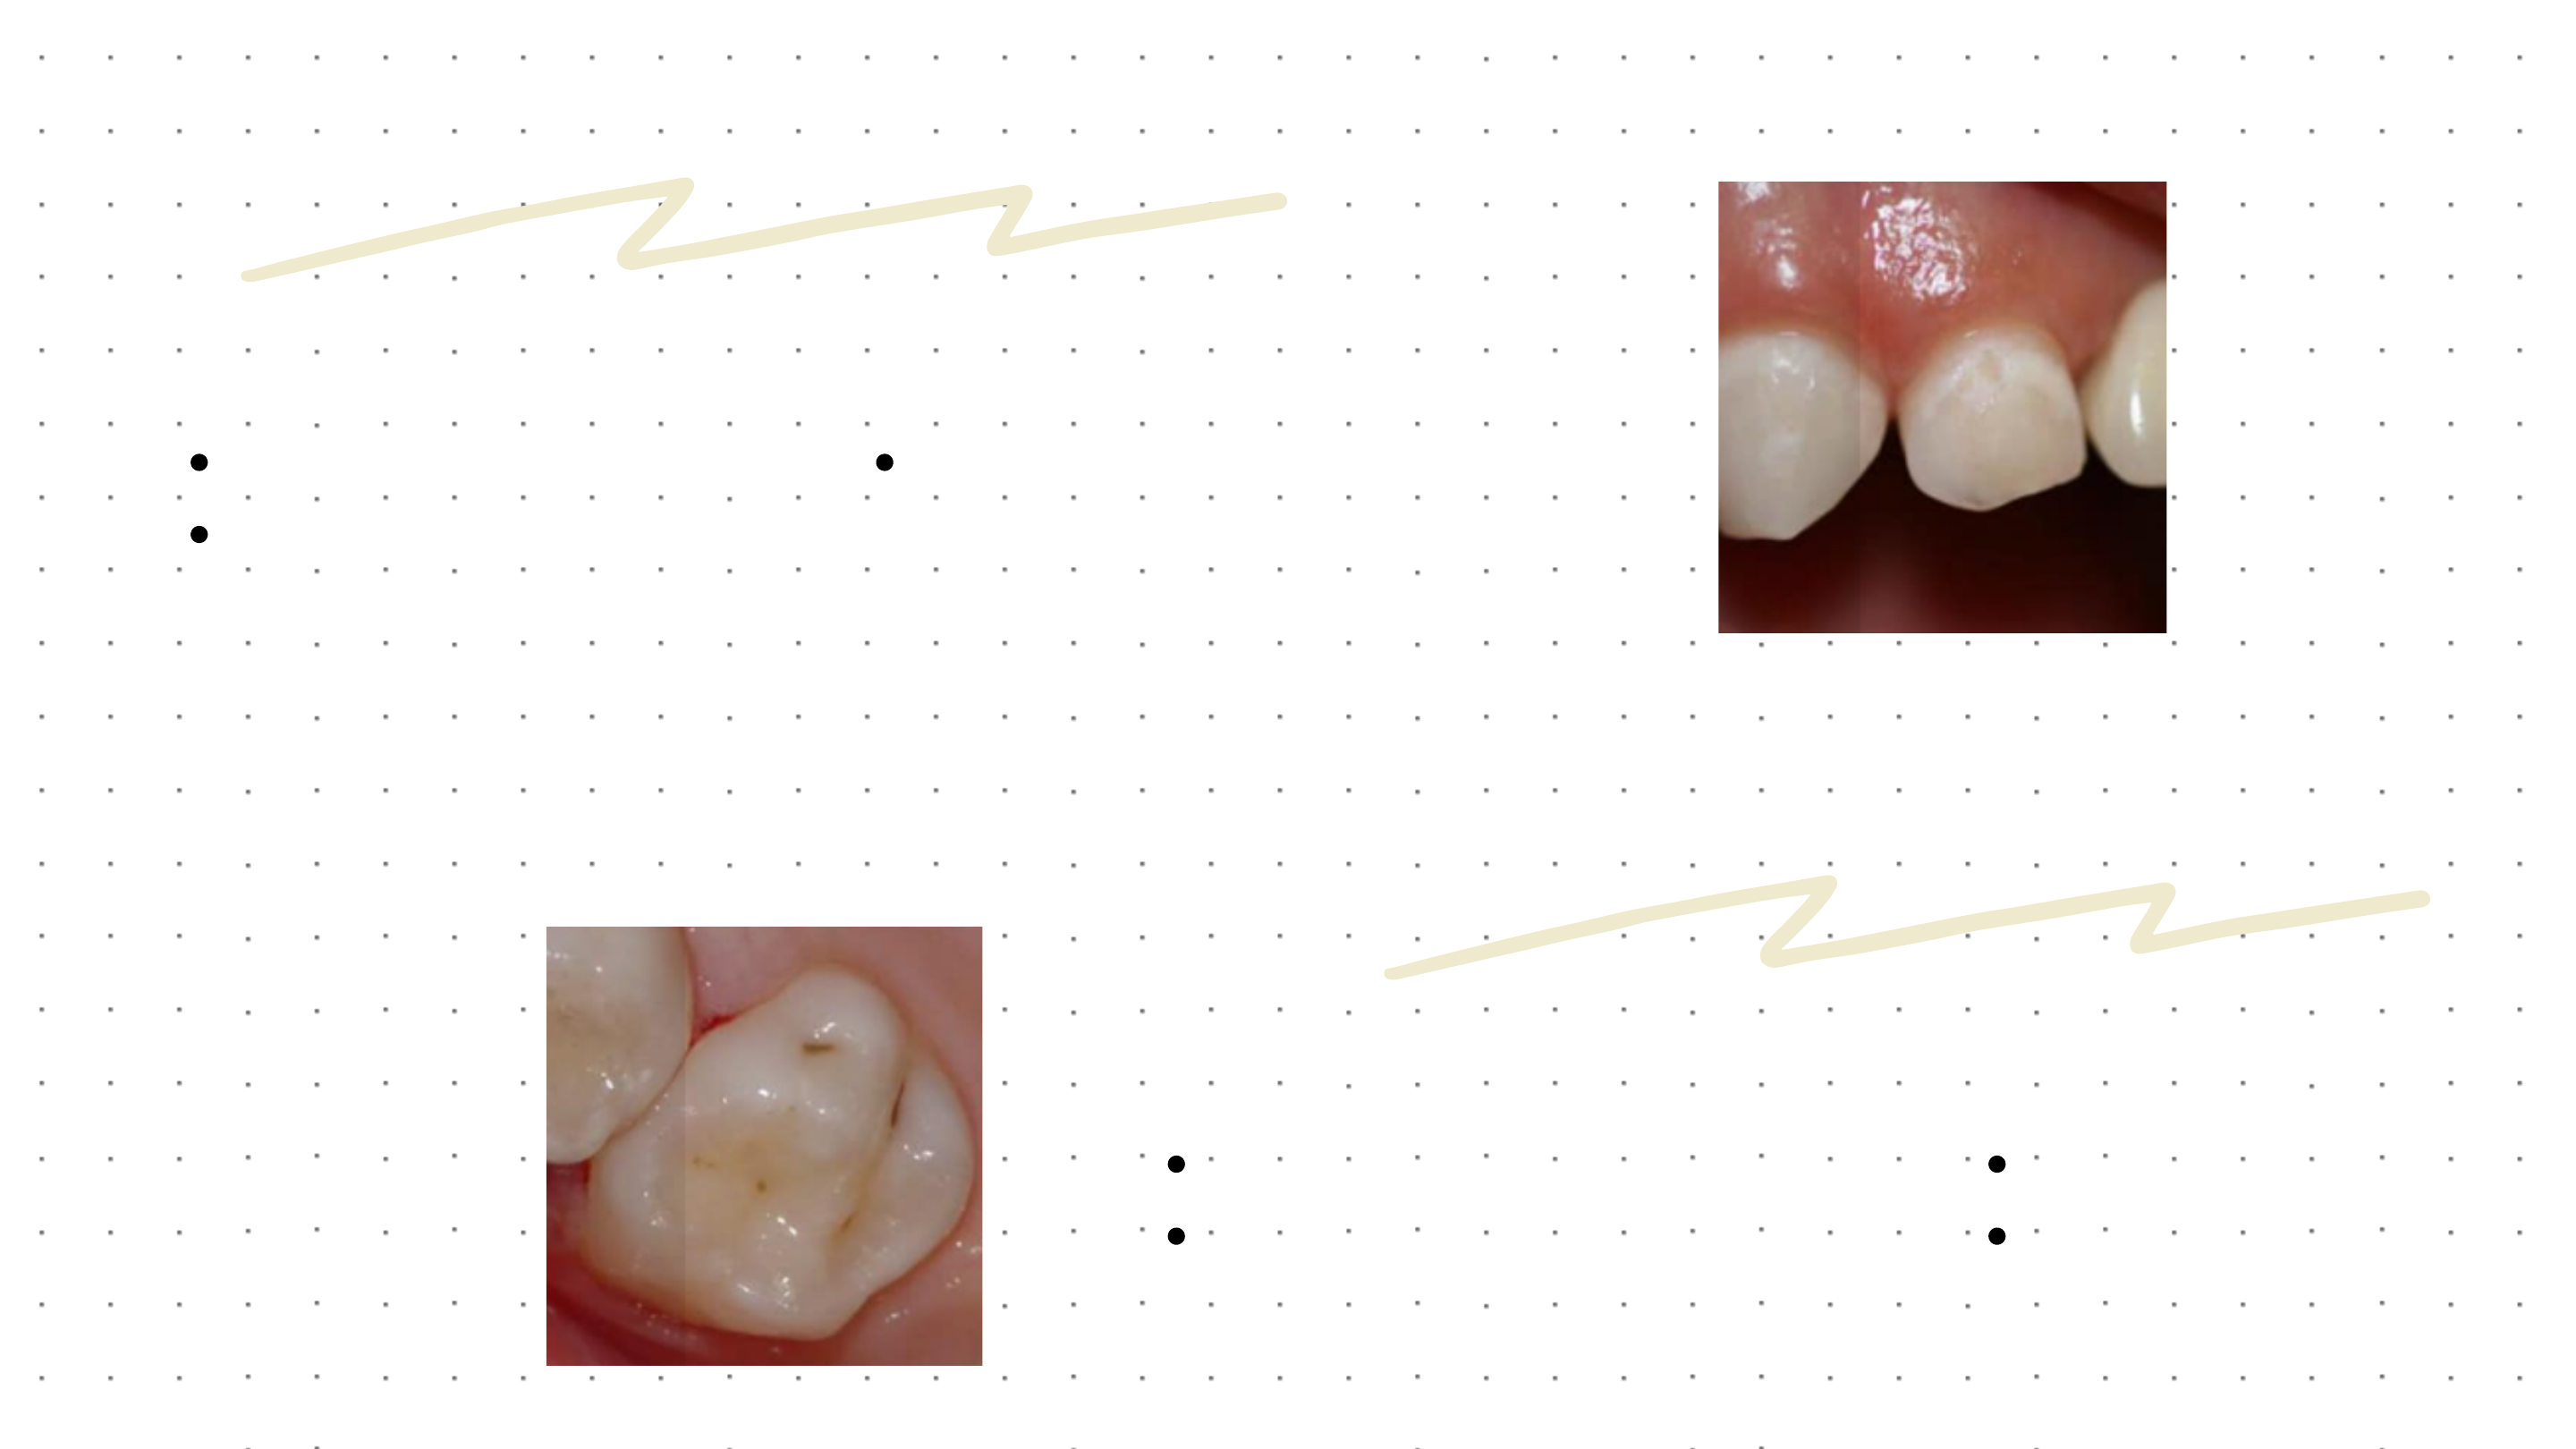

CÁRIE ATIVA

CÁRIE inATIVA

MANCHA BRANCA OPACA

SUPERFÍCIE RUGOSA

ASPECTO DO ESMALTE:

TECIDO AMOLECIDO DE

COLORAÇÃO MARROM

CLARA

ASPECTO DA DENTINA:

SUPERFÍCIA LISA M

ANCHA BRILHANTE E BRANCA

TECIDO DURO

ESCURECIDO